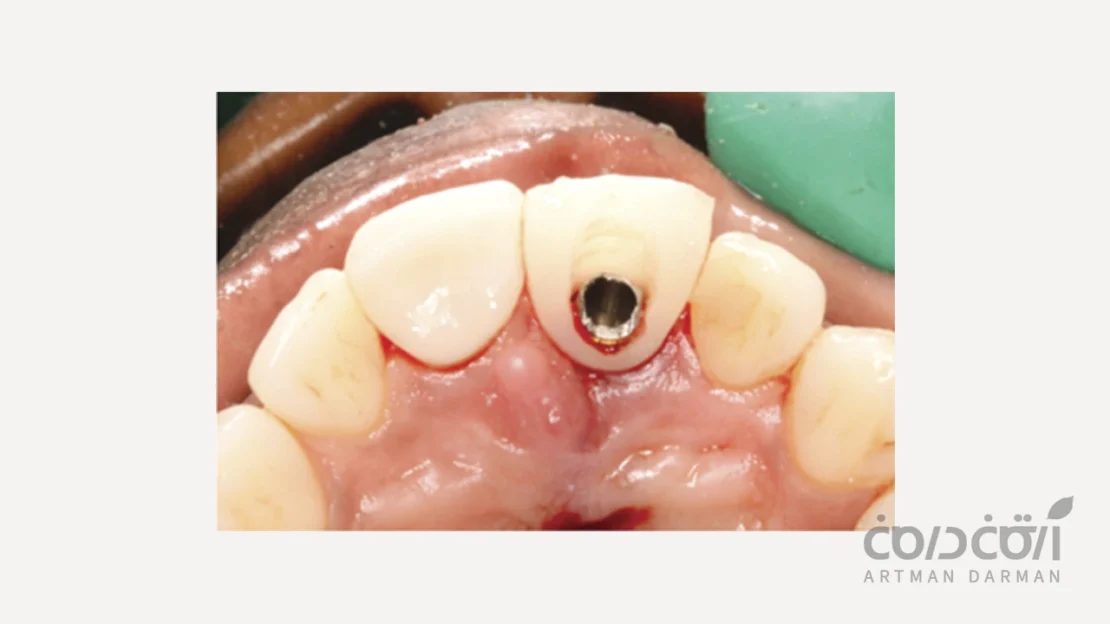

روکش موقت دندان

این پیشرفته ترین و در عین حال، حساس ترین نوع پروتز موقت ایمپلنت است. در این پروتز، یک روکش موقت سبک، بلافاصله پس از جراحی یا چند روز بعد، مستقیماً روی خود ایمپلنت قرار می گیرد. بسیار مهم است بدانیم که این روش تنها و تنها در شرایط کاملاً ایده آل قابل انجام است:

- ایمپلنت باید در حین جراحی به گیر مکانیکی بسیار بالایی در استخوان دست یافته باشد (معمولاً گشتاور بستن بالای 35 نیوتن سانتی متر).

- استخوان باید متراکم و سالم باشد.

- بیمار نباید عادت به دندان قروچه داشتهباشد.

مهم ترین اصل در خصوص روکش دندان موقت این است که …

این روکش موقت باید کاملاً خارج از تماس با دندان های مقابل (Out of Occlusion) باشد. یعنی هنگام بستن دهان یا جویدن، هیچ گونه تماسی بین این روکش و دندان های فک مقابل نباید وجود داشته باشد. روکش موقت صرفاً نقش زیبایی و فرم دهی به لثه را دارد.

بزرگترین ریسک در خصوص روکش دندان موقت هم این است ….

اگر بیمار احتیاط نکند و با آن غذای سفت بجود، فشار حاصل می تواند منجر به شکست کامل اوسئواینتگریشن و از دست رفتن ایمپلنت شود. این بزرگترین خطر در استفاده از این نوع پروتز موقت ایمپلنت است.